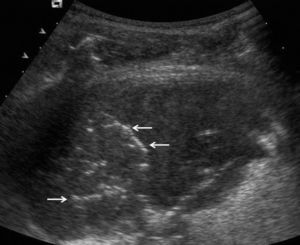

El aspecto ecográfico de un derrame pleural depende de su naturaleza, causa y cronicidad. Por sus características ecográficas los derrames pueden dividirse según presenten ecos internos, septos (gruesos o finos y móviles) y/o nodularidad pleural, o sean totalmente anecogénicos. Se ha demostrado que la ecografía es más sensible que la TC para demostrar la existencia de septos (fig. 1) en el interior de un derrame pleural4,18. La presencia de ecos, septos o nódulos permite catalogarlo de exudado19. La ausencia de estos hallazgos, es decir, el hecho de que se trate de un líquido anecogénico, no permite determinar que sea un trasudado, dado que los exudados se pueden presentar de esta manera19.